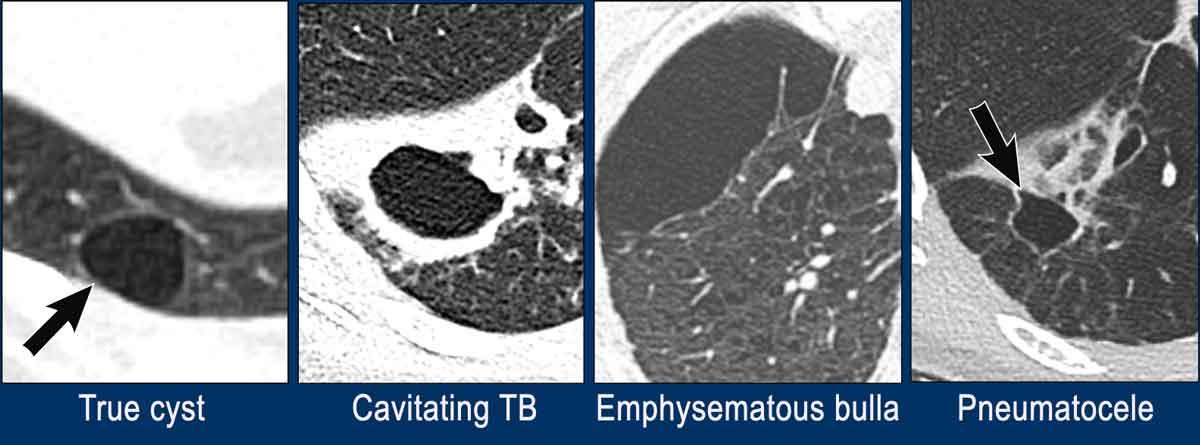

Nang phổi là bất kỳ cấu trúc chứa khí có giới hạn rõ nào trong nhu mô phổi với thành mỏng (< 2 mm) và thường đều đặn.

Trong hình minh họa là một số tổn thương đơn độc có thể giả dạng nang phổi.

- Nang phổi thực sự đơn giản với thành mỏng, nhẵn.

- Hang với thành dày, không đều trong trường hợp lao phổi.

Hình ảnh này cũng có thể gặp trong ác tính, các nhiễm trùng khác hoặc viêm mạch. - Bóng khí phế thũng (bulla) không có thành ở bệnh nhân khí phế thũng trung tiểu thùy.

- Phế nang khí (Pneumatocele). Có thể trông giống nang đơn giản, nhưng thường có tiền sử chấn thương ngực, thở máy với chấn thương áp lực hoặc nhiễm trùng.